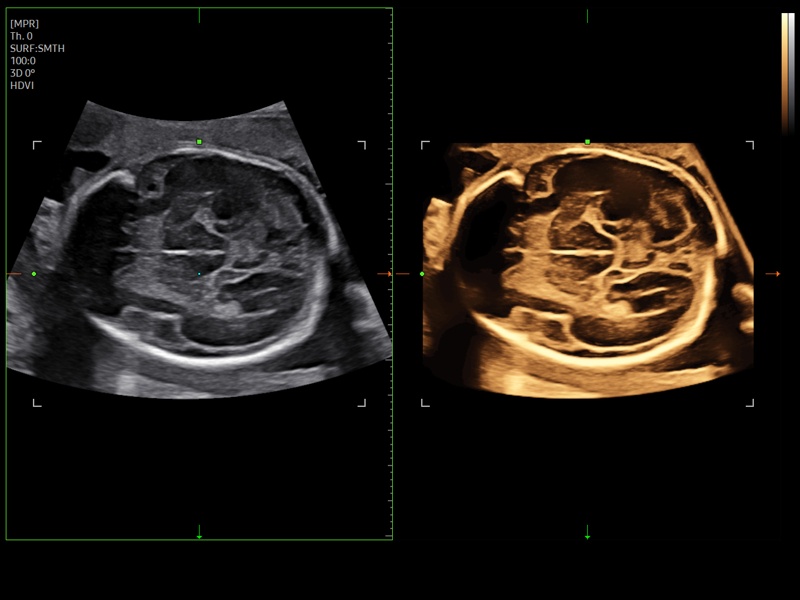

Fetal brain, Slice A (echogramm №943)

[RU] Ultrasound image №943: Fetal brain (neurosonogram) in Slice A mode.

Echogramm was received by ultrasound scanner Z20 (new model).